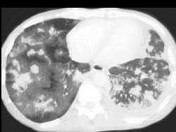

- 单项选择题女,26岁, 全身不适,发热, 咳嗽,咯血, 有吸毒史,结合CT图像, 最可能的诊断是 ( )

A、卡波济肉瘤

B、肺癌

C、肺转移癌

D、肺结节病

E、肺结核